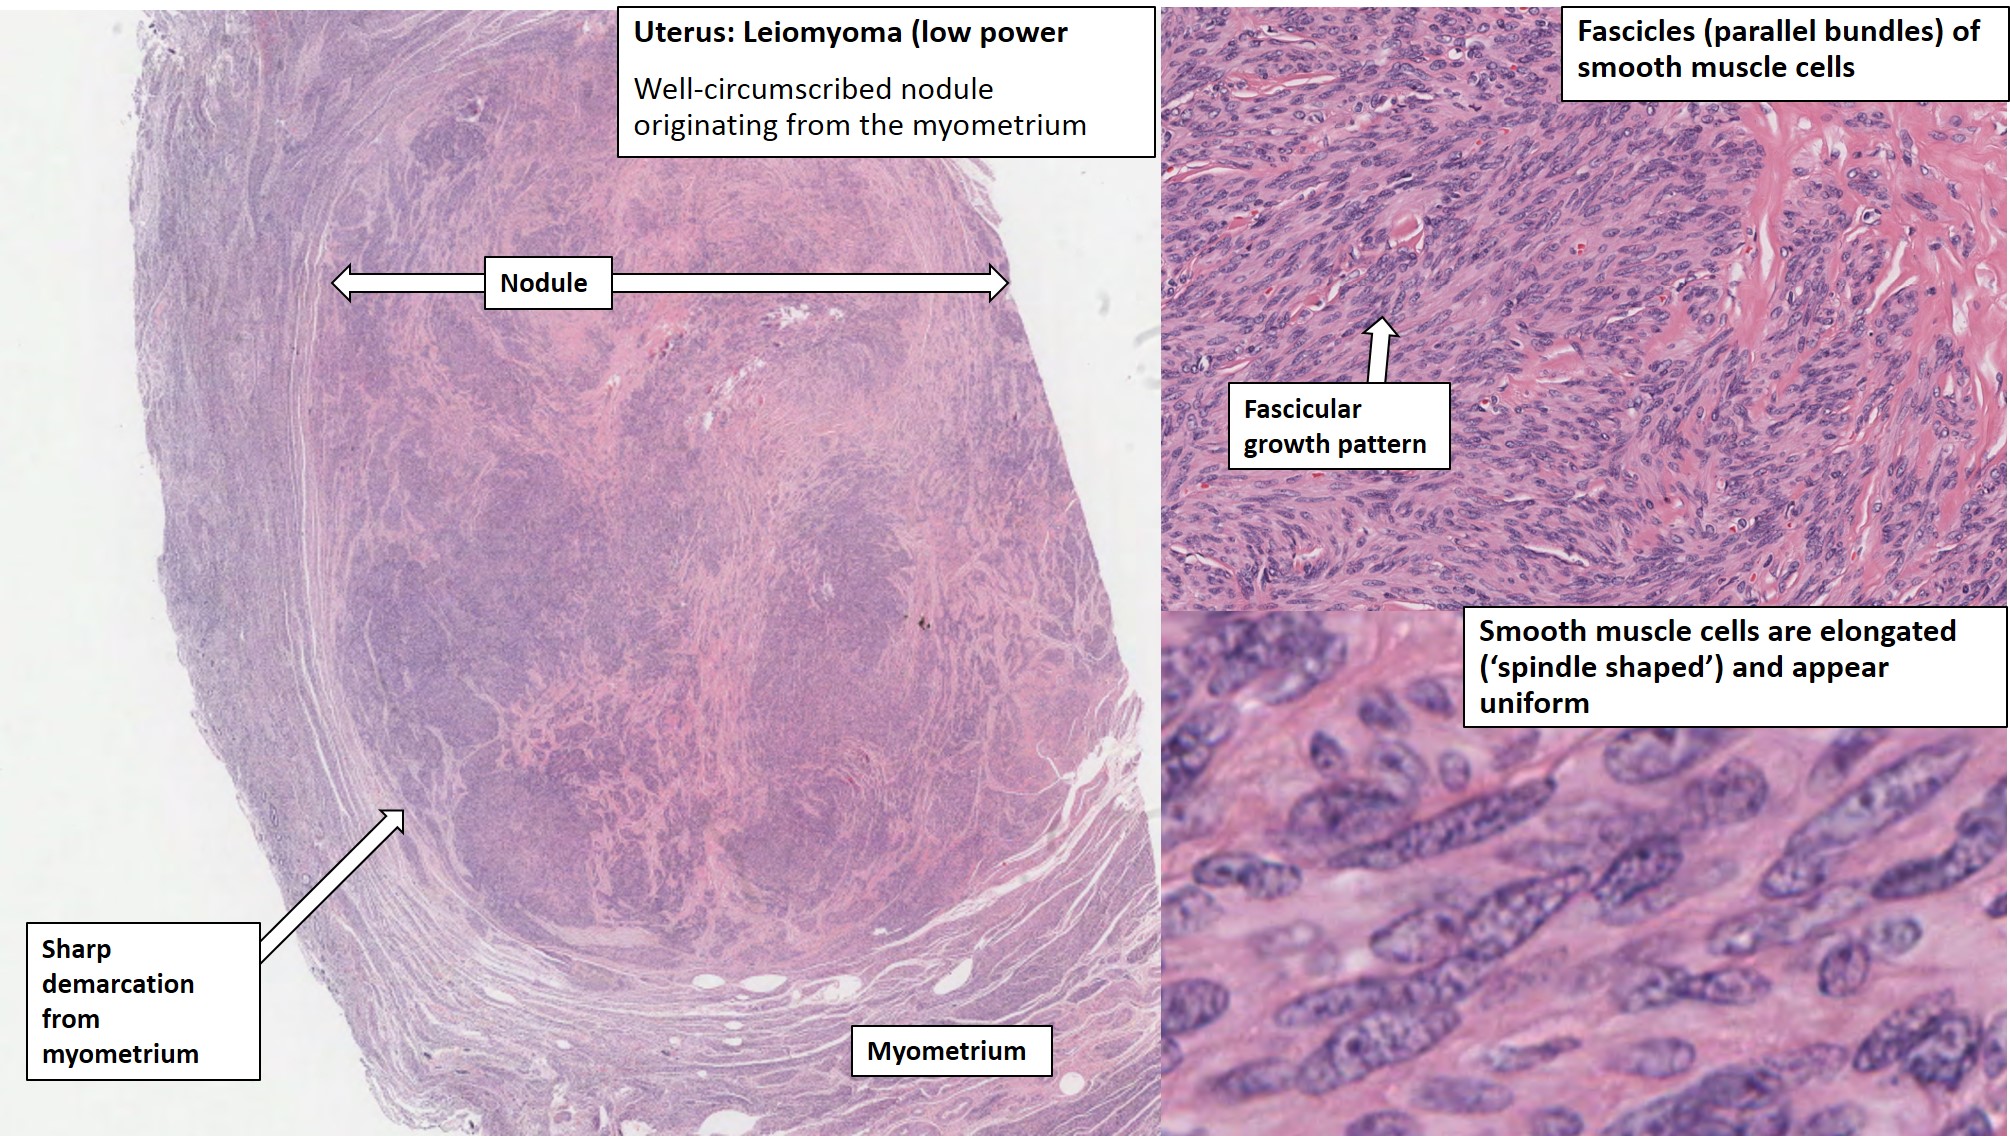

Leiomyoma Of The Uterus | Ottawa Atlas Of Pathology

www.pathologyatlas.ca

www.pathologyatlas.ca

Pathology Of Uterine Leiomyoma - Pathology Made Simple

ilovepathology.com

ilovepathology.com

leiomyoma uterine pathology microscopic cellular dissecting leiomyomas variants mitotically bizzare nuclei epithelioid lipomatous myxoid hydropic include ilovepathology

Leiomyomata Uteri (Uterine Leiomyoma) - Stepwards

www.stepwards.com

www.stepwards.com

uterus leiomyoma histology uterine uteri stepwards cat pathology cells normal figure fibroid female muscle analysis smooth resemble bmj

Leiomyoma (Uterus) – BosnianPathology

www.bosnianpathology.org

www.bosnianpathology.org

Uterus: Leiomyoma

atlasgeneticsoncology.org

atlasgeneticsoncology.org